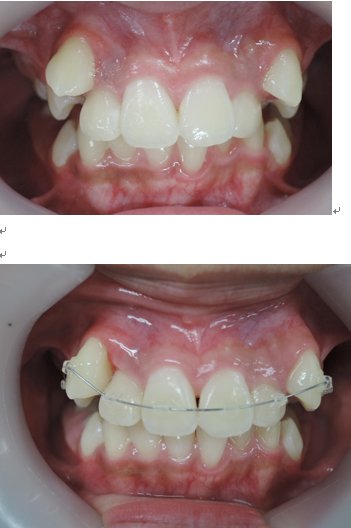

以下の上顎の症例では左右の第一小臼歯を抜かないと治療出来ないと説明があるはずです。しかし、当院での治療終了時には顎骨が拡大して綺麗に歯が並んでいます。

初診時 終了時

治療期間3年0か月で機能的で美しい咬み合わせが完成しました。

今回の症例は一般的に抜歯(第一小臼歯)が必要な症例ですが当院では非抜歯で治療する事が出来ました。